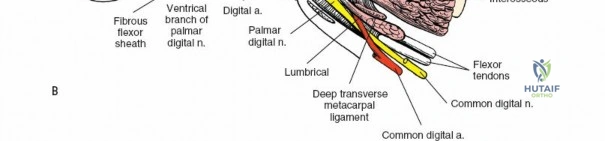

A thorough understanding of the intricate anatomy and biomechanics of the flexor tendon system is non-negotiable for any surgeon employing a volar approach. The digital flexor system comprises the Flexor Digitorum Superficialis (FDS) and Flexor Digitorum Profundus (FDP) tendons. The FDP tendon originates from the ulna and interosseous membrane, inserting onto the volar base of the distal phalanx, primarily responsible for DIP joint flexion. The FDS tendon originates from the medial epicondyle, ulna, and radius, typically bifurcating around the FDP in the region of the proximal phalanx (Camper's chiasm) before inserting onto the middle phalanx, primarily flexing the PIP joint.

Within the fibro-osseous tunnel, these tendons are enveloped by a synovial sheath that facilitates smooth gliding and nutrition. The integrity of the pulley system, composed of annular (A) and cruciate (C) ligaments, is critical for preventing tendon bowstringing and maintaining efficient mechanical advantage. Typically, five annular pulleys (A1-A5) and three cruciate pulleys (C1-C3) are described in each finger. The A1 pulley is at the metacarpophalangeal (MCP) joint level, A2 at the proximal phalanx, A3 at the proximal interphalangeal (PIP) joint, A4 at the middle phalanx, and A5 at the distal interphalangeal (DIP) joint. The A2 and A4 pulleys are considered the most critical for preventing significant bowstringing.

The digital neurovascular bundles (NVBs) run along the radial and ulnar sides of each digit, volar to the collateral ligaments, providing sensation and vascularity. Proper identification and protection of these bundles are paramount during any volar dissection. Proximally, the median nerve gives rise to recurrent motor branches to the thenar muscles and sensory branches to the thumb, index, middle, and radial half of the ring finger. The ulnar nerve supplies the hypothenar muscles, adductor pollicis, and interossei, along with sensory innervation to the little finger and ulnar half of the ring finger. The palmar arches (superficial and deep) provide critical vascular supply to the hand.

After marking the incision, the skin and subcutaneous tissues are carefully incised. In the digits, the triangular skin flaps created by the Bruner incision are elevated using fine skin hooks or small self-retaining retractors. Dissection should proceed in the subcutaneous plane, superficial to the digital neurovascular bundles, which run along the radial and ulnar borders of the digit, immediately adjacent to the flexor sheath.

Care must be taken to identify and protect these bundles. Any existing lacerations or hematomas are debrided. The digital nerves and vessels are carefully dissected free from the surrounding connective tissue and retracted, typically dorsally and laterally, using vessel loops or fine retractors to provide clear access to the underlying flexor sheath.